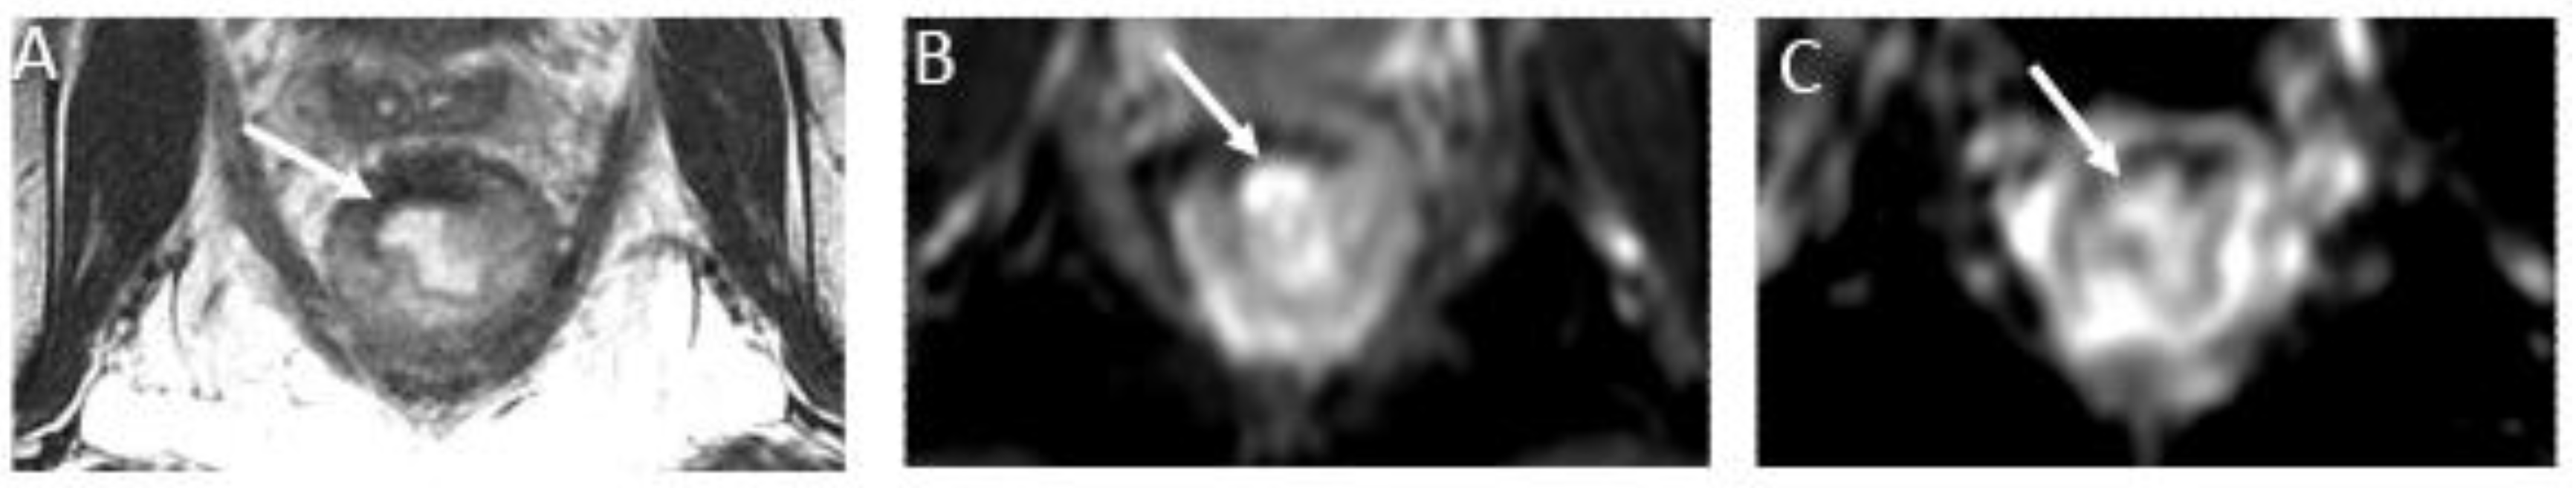

b) nCR serves as a transitional state between CR and other responses, with substantial regression evident. The concept of a "near-complete response" has emerged more recently, driven by the observation that a significant proportion of patients initially displaying a very good yet incomplete response during the first assessment may ultimately achieve a complete clinical response when provided with a longer interval before re-assessment (26) (Figure 3). However, it retains a trace of diffusion restriction post-neoadjuvant therapy, underscoring ongoing positive changes. In cases where tumor signal or diffusion restriction persists after one or two short-term follow-up evaluations, the case should be reclassified as iCR and considered unsuitable for observation.

Figure 3. Near complete response in a 65-year-old man with middle rectal adenocarcinoma. (A) Baseline axial T2-weighted MR image shows an intermediate-signal-intensity, near-circumferential low rectal tumor (dotted line). (B) Axial T2-weighted MR image after completion of neoadjuvant chemoradiotherapy shows a slight response with a small amount of fibrosis and residual tumor signal intensity (arrow). Axial diffusion-weighted image (C) shows high signal intensity (arrowhead), and axial ADC map (D) shows corresponding low signal intensity (arrowhead), in keeping with restricted diffusion at the nonfibrotic portion of the tumor.